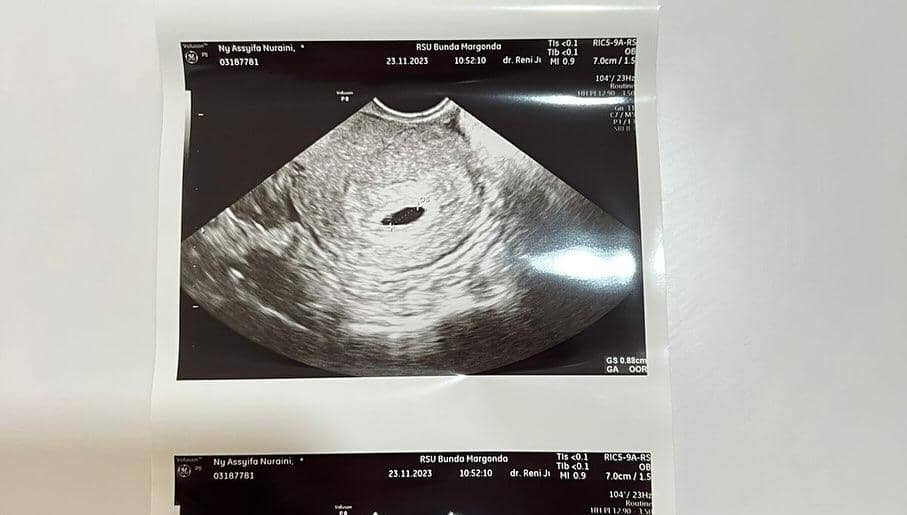

Tak hanya mengunggah video, Umi Kalsum juga mengunggah beberapa foto termasuk pula hasil foto ultrasound calon cucu ketiganya itu.

Tak hanya memperlihatkan janin yang ada di dalam perut Syifa, Umi Kalsum juga menginformasikan usia kandungan putrinya itu kepada publik.

"Sampai hari ini periksa kembali di @rsubunda.margonda karena drop kesehatannya @syifaasyifaaa kehamilan ke-2 ini di rawat 1 hari saja. Sudah memasuki kehamilan 2 bulan dan sudah jelas banget cabang bayi dalam kandungan kamu. Sehat y nak kamu dan cabang bayi dalam kandungan kmu Aamin y robbal Alamin," ungkapnya lagi.